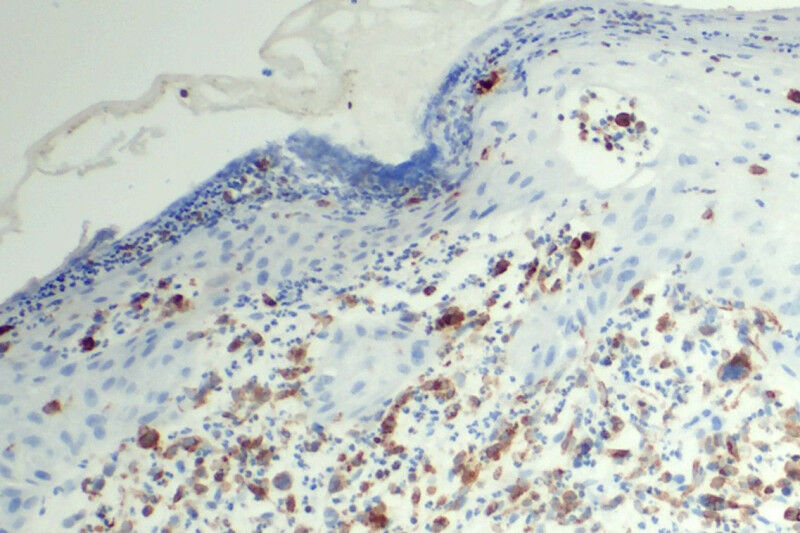

A team of researchers from MedUni Vienna led by Olaf Merkel and the Experimental and Clinical Research Center (ECRC), a joint institution of Charité and the Max Delbrück Center, led by Stephan Mathas has shown in a new study that the CD74 protein expressed on CTCL cells is a promising target for innovative therapies. The study showed that so-called antibody-drug conjugates (ADCs), which specifically bind to CD74, can effectively kill CTCL cells.

Curative treatment options for cutaneous T-cell lymphomas are still lacking. Although monoclonal antibodies and ADCs are already being used, the spectrum of targetable cell surface structures is limited. The new study shows that CD74 is strongly and consistently expressed in various CTCL subtypes, including particularly difficult-to-treat forms such as Sézary syndrome and advanced stages of mycosis fungoides.